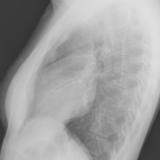

Part'l abs peric Lat